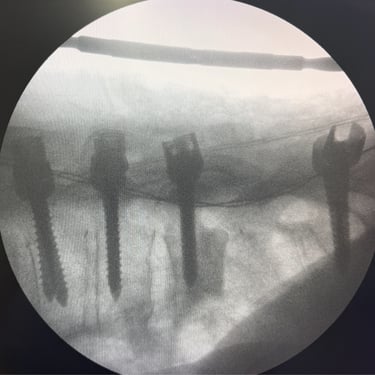

🧠Listesis Lumbar L5–S1 por Fractura Ístmica: Estabilización con FTP y TLIF.

La listesis L5–S1 por fractura ístmica causa inestabilidad y dolor. El tratamiento quirúrgico con FTP y TLIF permite descompresión neural y estabilización vertebral, mejorando la función y calidad de vida.